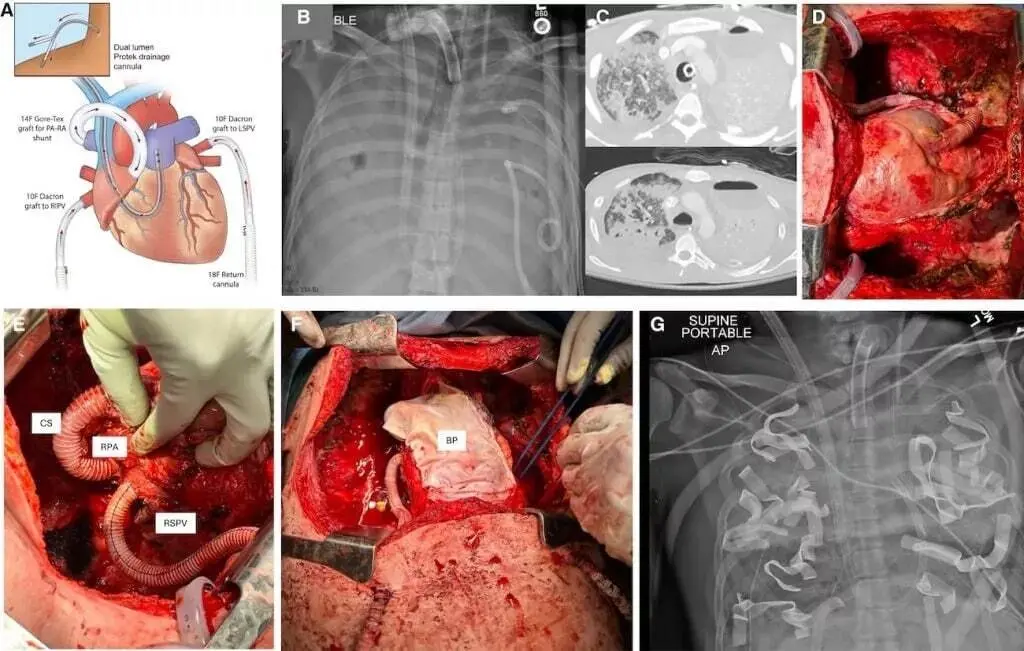

براساس گزارش ساینسآلرت، پزشکان با ساخت یک سیستم ریه مصنوعی کامل (TAL) توانستند وظیفه اکسیژنرسانی به خون را دقیقاً مانند ریههای طبیعی انجام دهند. این دستگاه علاوهبر اکسیژنرسانی، جریان خون را مدیریت و از قلب محافظت میکند.

رویکرد معمول در این شرایط، اتصال بیمار به دستگاههای حمایت حیاتی است تا ریهها ترمیم شوند؛ اما در این مورد خاص، خود ریهها عامل مرگ بودند و تحلیلهای مولکولی نشان داد که تخریب بافتی غیرقابلبازگشت است. بنابراین تنها راه نجات، خارجکردن منبع عفونت (ریهها) پیش از انجام پیوند بود.

برداشتن هر دو ریه معمولاً به دلیل اختلال شدید در جریان خون، باعث نارسایی قلبی میشود. برای جلوگیری از این اتفاق، تیم پزشکی در طراحی سیستم TAL، کانالهای جریان خون دوگانه و یک شانت را اضافه کردند تا نوسانات جریان خون را هموار کنند. این دستگاه توانست بیمار را زنده نگه دارد تا بدنش پس از حذف منبع عفونت ریکاوری و برای دریافت پیوند آماده شود. پس از خارجکردن اندامهای عفونی، علائم بهبودی از عفونت بلافاصله در بدن بیمار نمایان شد.